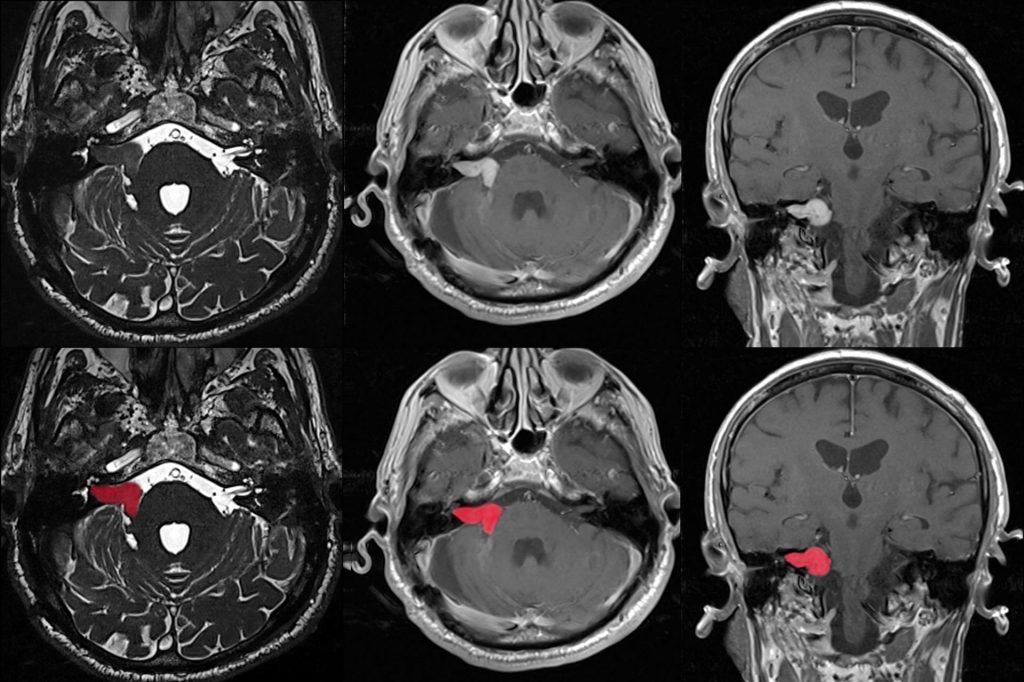

- Bildgebung (MRT-Scan)

Beim Auftreten von asymmetrischen Hör- und Gleichgewichtssymptomen, wird immer ein bildgebender Test angeordnet, um ein Akustikusneurinom auszuschließen. Eine MRT-Untersuchung mit Kontrastmittel (Gadolinium-Farbstoff) ist der Goldstandard für die Diagnose eines Akustikusneurinoms. Dabei können sehr kleine Tumore entdeckt werden, die ohne eine MRT mit Kontrastmittel vielleicht gar nicht bemerkt worden wären.